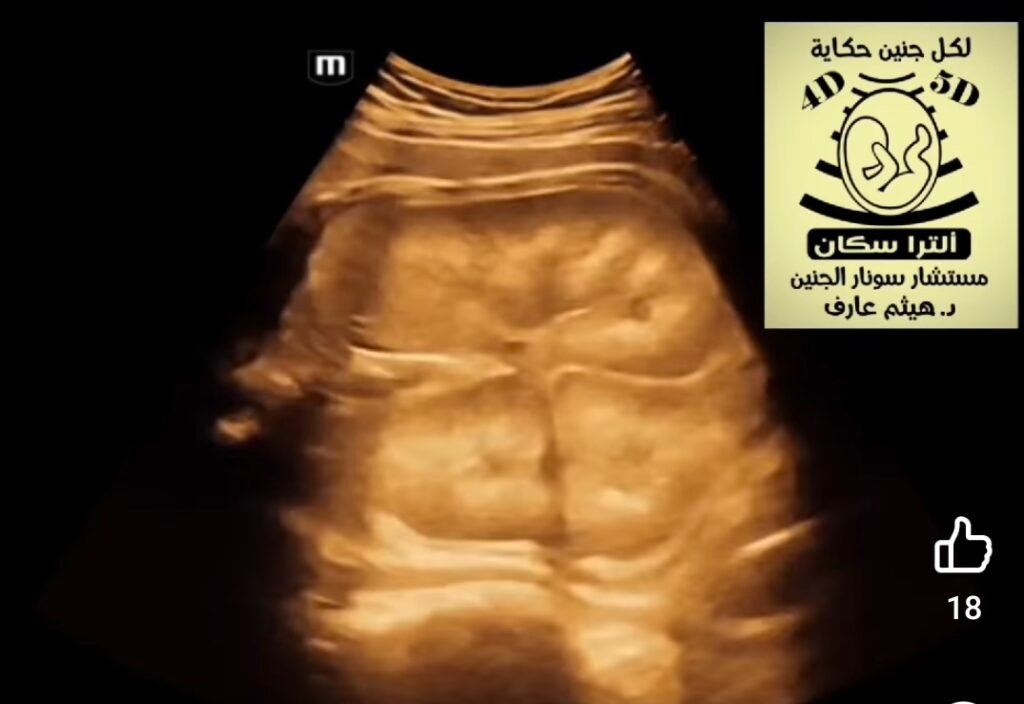

Fetal ultrasound for Auto somal Recessive Polycystic Kidney Disease (ARPKD) typically reveals symmetrically enlarged, highly echogenic (bright) kidneys, often detectable by the second trimester (around 18-24 weeks). The kidneys frequently show a “salt-and-pepper” or heterogeneous texture due to tiny cysts, leading to significantly reduced amniotic fluid (oligohydramnios).  Ultrasound Findings (ARPKD):Renomegaly: Significantly enlarged kidneys (nephromegaly) that may fill the abdomen.Echogenicity: Hyperechoic (bright) kidney parenchyma, often without clear separation between the cortex and medulla.Cysts: While the disease is cystic, the cysts are often microscopic or too small to resolve (typically  cm), differentiating it from the larger cysts in Autosomal Dominant PKD (ADPKD).Oligohydramnios: Decreased amniotic fluid, which is a significant indicator, often leading to pulmonary hypoplasia.Reversed corticomedullary differentiation: The medulla may appear brighter than the cortex. Timing and Progression:Early Detection: While sometimes seen earlier, characteristic findings are usually prominent in the second half of pregnancy.Serial Scans: Serial ultrasounds are used to monitor kidney enlargement and amniotic fluid appearance of ARPKD can overlap with other conditions. Similar findings include: Autosomal Dominant Polycystic Kidney Disease (ADPKD).Meckel-Gruber syndrome.Congenital nephrotic syndrome